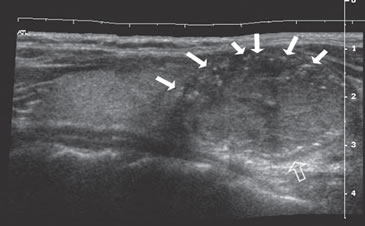

La extensión de la masa fuera de la cápsula, la infiltración de la tráquea o de los músculos pretiroideos es muy sugerente de malignidad (Figura 15a). Asímismo, la presencia de adenopatías con características típicas, debe hacer sospechar que el nódulo tiroideo es maligno. Los cánceres papilares de la tiroides son propensos a dar metástasis precozmente a los linfonodos cervicales y hasta la mitad de todos los pacientes pueden presentar adenopatías concomitantes. En 15% de los pacientes, el único signo de un cáncer tiroideo papilar oculto puede ser la detección de adenopatías. La mayoría de las metástasis ocurren ipsilateralmente al tumor primario en los grupos III y IV de la cadena yugular interna y del grupo VI del compartimiento central. En la ecografía, los linfonodos metastáticos pueden tener una forma redondeada o globular, una arquitectura con elementos sólidos o quísticos, con o sin microcalcificaciones y pérdida del hilio (Figura 15b y c). El “Doppler color” puede demostrar vasos capsulares de distribución caótica en reemplazo de los vasos hiliares normales (Figura 15d). Las adenopatías hiperecogénicas son sospechosas de cáncer papilar (Figura 16a). Los linfonodos normales en algunos grupos como el VI y el VII no se ven ecograficamente, de manera que si se hacen visibles, en el mismo lado del tumor, independiente del tamaño que tengan hay que considerarlos como adenopatías metastásicas (Figura 16b)

Figura 15. a) Cáncer papilar sólido de bordes lobulados (flechas) que muestra una gruesa calcificación central (flecha abierta) y múltiples

microcalcificaciones; b) Adenopatía cervical del grupo IV del mismo paciente (figura 15 a), hiperecogénica, con elementos quísticos (flecha

blanca) y microcalcificaciones agrupadas (flechas negras), típica de cáncer papilar; c) Adenopatías de grupo IV de un cáncer papilar, de

forma redondeada, hiperecogénicas, con pérdida del hilio, una anterior a la arteria carótida común (flecha) y otra lateral a la vena yugular

interna (flecha abierta); d) Corte sagital de la adenopatía lateral de la imagen 15 c), que en “doppler color” muestra vascularización patológica

y pérdida del hilio.